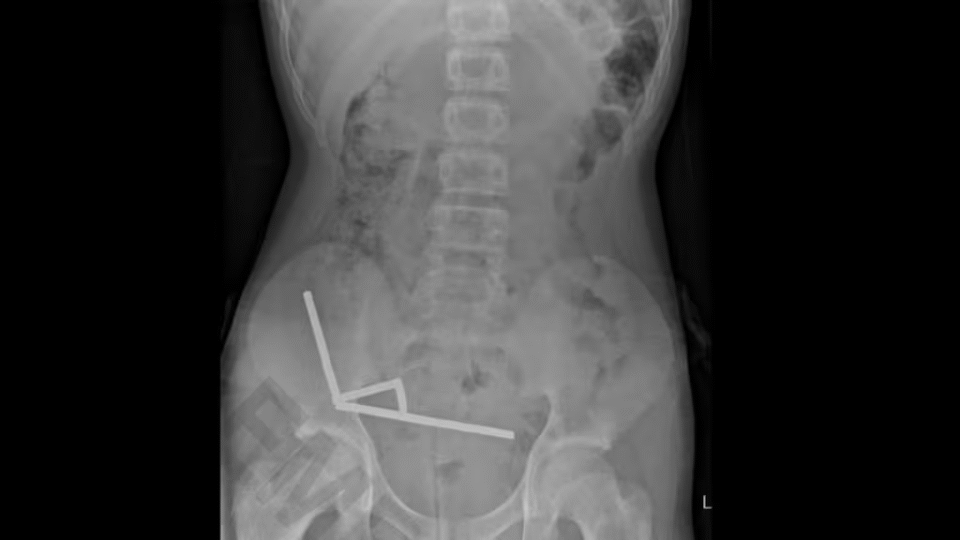

ਆਕਲੈਂਡ (ਐੱਨ ਜੈੱਡ ਤਸਵੀਰ) ਇਕ 13 ਸਾਲਾ ਲੜਕੇ ਦੀ ਟੌਰਾਂਗਾ ਹਸਪਤਾਲ ਵਿੱਚ ਵੱਡੀ ਸਰਜਰੀ ਕੀਤੀ ਗਈ, ਜਦੋਂ ਉਸ ਨੇ ਟੇਮੂ (Temu) ਤੋਂ ਖਰੀਦੇ 80 ਤੋਂ 100 ਛੋਟੇ ਮੈਗਨਿਟ ਨਿਗਲ ਲਏ। ਨੀਓਡਿਮਿਯਮ (Neodymium) ਮੈਗਨਿਟਾਂ ’ਤੇ 2014 ਤੋਂ ਪਾਬੰਦੀ ਹੈ, ਪਰ ਇਹ ਅਜੇ ਵੀ ਆਨਲਾਈਨ ਮਾਰਕੀਟਪਲੇਸਾਂ ’ਤੇ ਉਪਲਬਧ ਹਨ।

ਨਿਊਜ਼ੀਲੈਂਡ ਮੈਡੀਕਲ ਜਰਨਲ ਵਿੱਚ ਪ੍ਰਕਾਸ਼ਿਤ ਕੇਸ ਅਧਿਐਨ ਅਨੁਸਾਰ, ਸਰਜਨਜ਼ ਨੂੰ ਲੜਕੇ ਦੀਆਂ ਆਂਤਾਂ ਦਾ ਇਕ ਹਿੱਸਾ ਕੱਟਣਾ ਪਿਆ ਕਿਉਂਕਿ ਉਸ ਨੇ ਇਹ ਛੋਟੇ ਮੈਗਨਿਟ ਨਿਗਲ ਲਏ ਸਨ।